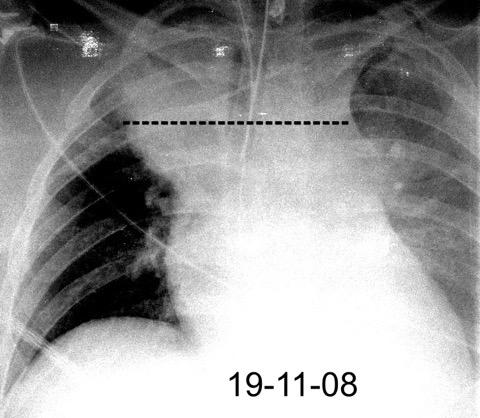

85. ENSANCHAMIENTO MEDIASTÍNICO AGUDO

102. HEMATOMA MEDIASTÍNICO.

Rotura traumática aórtica.Hematoma toracoabdominal